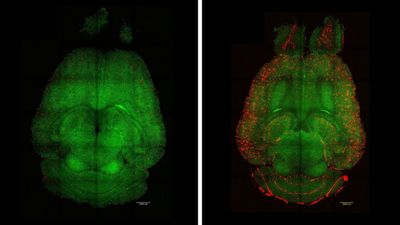

Ученые обнаружили, что воздействие на спящие гены обращает вспять снижение когнитивных функций. Открытие предлагает новые возможности для профилактики и лечения деменции, а также указывает на необходимость целостного подхода в изучении природы нейродегенерации.

Очищение мозга от токсичных белков недостаточно для победы над болезнью Альцгеймера

Ученые пришли к выводу, что удаление белков амилоида из ткани головного мозга хоть и приводит к некоторым положительным изменениям, но такая стратегия не может восстановить утраченные функции. Результаты исследования вновь демонстрируют, что природа нейродегенерации намного сложнее, чем принято считать.